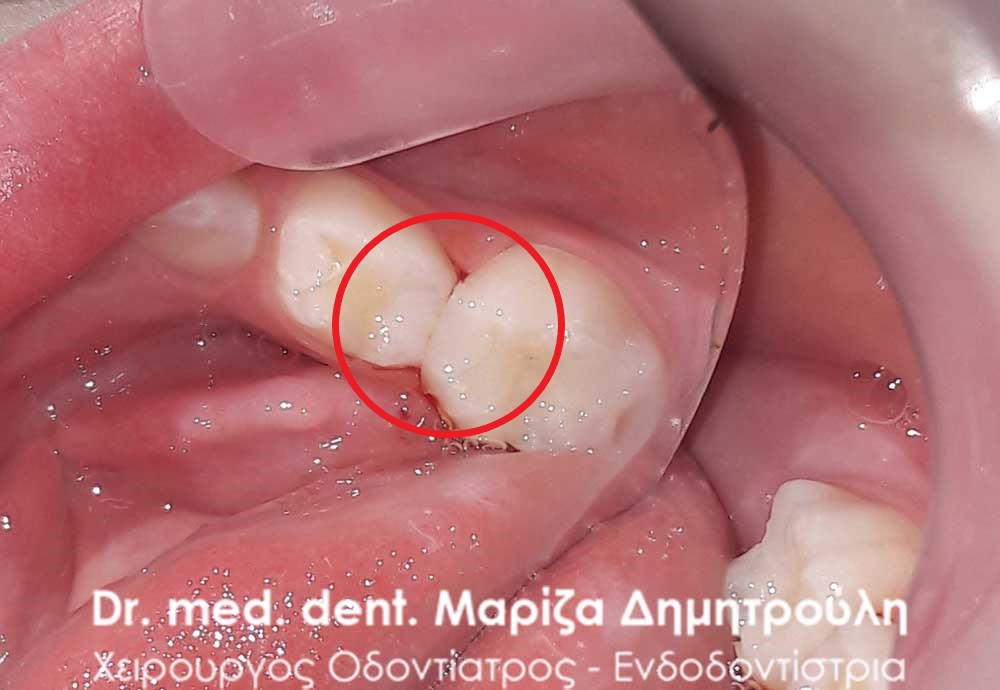

Περιστατικό – Σφραγίσματα παιδικών δοντιών

Κορίτσι ηλικίας 9 ετών αναφέρει οτι πονάει στην πάνω αριστερή πλευρά του στόματος της όταν μασάει. Μετά την κλινική εξέταση διαπιστώθηκε η ύπαρξη 2 τερηδονισμένων δοντιών. Στον πρώτο μόνιμο αριστερό γομφίο είναι εμφανής η ύπαρξη τερηδόνας, της οποίας η έκταση αποδείχτηκε αρκετά βαθιά κατά τη διάνοιξη του δοντιού. Στο δεύτερο νεογιλό (παιδικό) γομφίο παρατηρήθηκε η ύπαρξη τερηδονικής κοιλότητας μεσαίου βάθους.

Μετά την απομάκρυνση της τερηδόνας από τα δύο δοντάκια πραγματοποιήθηκαν λευκά σφραγίσματα σύνθετης ρητίνης.

ΠΡΙΝ

ΜΕΤΑ